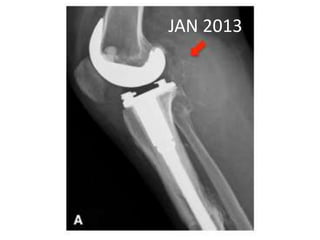

JAN 2013

• MAY 2013 •DENOSUMAB started • 360 mg subcutaneous dose • Followed by 120 mg every month

• 48.

• 49.

• Pain aroundknee joint diminished • Further resection ?? • Patient refused • Clinical improvement persisted until jan 14 • Presented with Rapidly growing painful palpable mass • Open biopsy : high grade sarcoma • A/K amputation